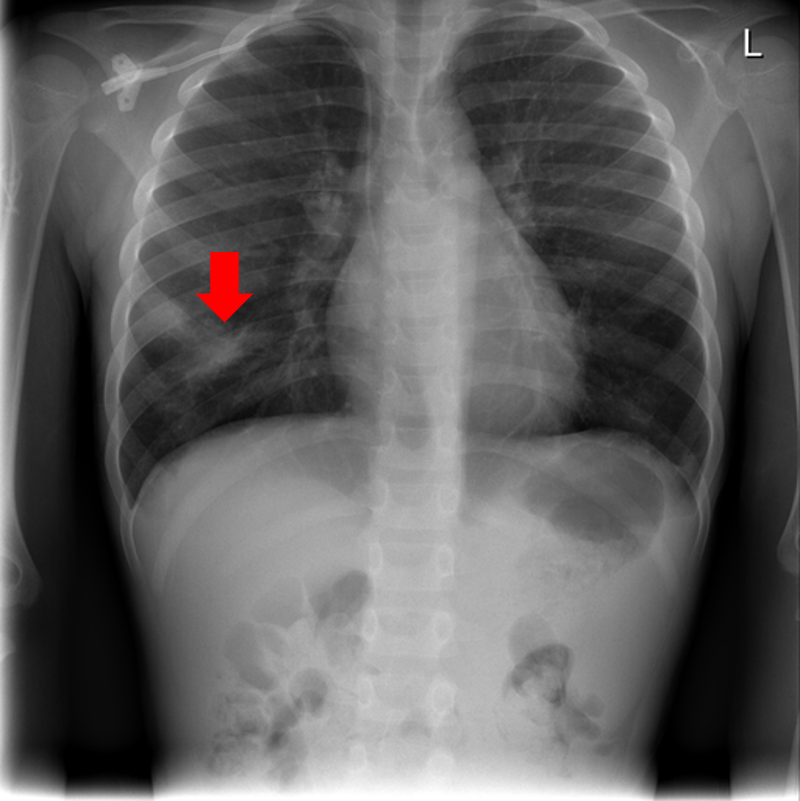

Figure 9: Typical CXRs with pneumonia-like lung opacity from among the top 1,000 CXRs most likely to have an abnormality according to the logarithm posterior probability out of the 13,863 abnormal CXRs. The lesion is indicated with a red arrow if applicable.

Figure 9 shows CXRs suggested to have pneumonia-like lung opacity with the logarithm posterior probability. These CXRs are the top 1,000 CXRs most likely to have an abnormality out of the 13,863 abnormal CXRs.